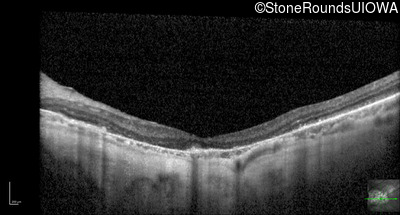

Optical Coherence Tomography - Right - 20/25 +1

Exemplar / OCT Stack

OCT Stack